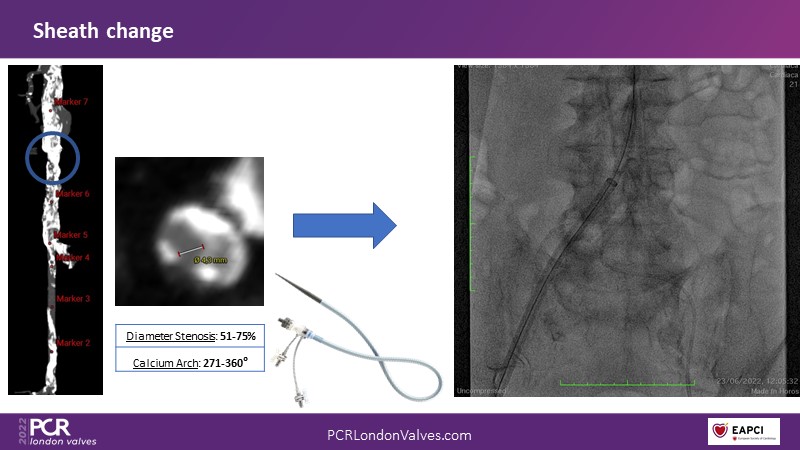

Transfemoral TAVI access using intravascular lithotripsy in patients with challenging peripheral vascular disease

- To understand how the unique mechanism of action of intravascular lithotripsy changes vessel compliance and mitigates procedural risk